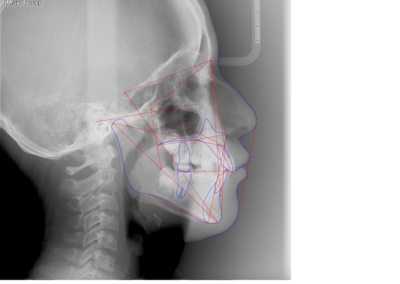

Many of us are not born with picture perfect teeth. For the straight teeth and alignment many people are searching for, braces is a common and effective treatment. Precision Dental Care uses the latest X-Ray technology to trace and model your teeth for your unique dental needs. From crooked teeth to alignment issues, braces can solve a variety of oral concerns.

Before and After Gallery